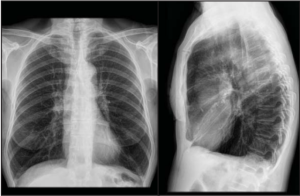

Na radiologia, os termos radiopaco e radiolúcido descrevem a capacidade de diferentes materiais absorverem ou permitirem a...